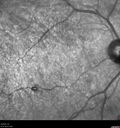

Congenital Hypetrophy of the Retinal Pigment Epithelium (CHRPE)621 views63 year old female with normal vision and CHRPE lesion in the right eye.Apr 27, 2020

Congenital Hypetrophy of the Retinal Pigment Epithelium (CHRPE)381 views63 year old female with normal vision and CHRPE lesion in the right eye.Apr 27, 2020

Congenital Hypetrophy of the Retinal Pigment Epithelium (CHRPE)365 views63 year old female with normal vision and CHRPE lesion in the right eye.Apr 27, 2020

Congenital Hypetrophy of the Retinal Pigment Epithelium (CHRPE)375 views63 year old female with normal vision and CHRPE lesion in the right eye.Apr 27, 2020

Congenital Hypetrophy of the Retinal Pigment Epithelium (CHRPE)376 views63 year old female with normal vision and CHRPE lesion in the right eye.Apr 27, 2020

Congenital Hypetrophy of the Retinal Pigment Epithelium (CHRPE)432 views63 year old female with normal vision and CHRPE lesion in the right eye.Apr 27, 2020